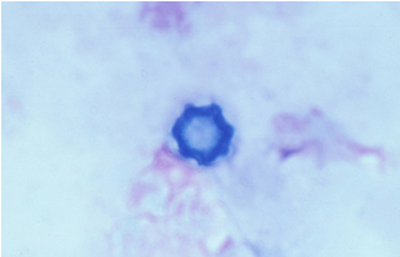

Coloración de Giemsa

En un frasco de Copli colocar 10 ml de la solución del colorante de Giemsa con 90 ml de un buffer fosfato 1/15 M y pH 6.8. Colorear el extendido fijado por 20 minutos. Lavar en agua corriente y dejar secar al aire. Aclarar en xileno por 5 minutos y montar con un medio de resina.

Los quistes Acanthamoebas midien de 10 a 16 µm de diametro, con capsula de forma circular o poligonal, a veces con angulaciones y ondulaciones, (Figura 41) teñido densamente azul oscuro. Membrana plasmática con tinción más tenue, concéntica, o retraida o colapsada asimétricamente. Coloración variable del citoplasma. (Figura 42, 43, 44 y 45)

Fig. 41 Giemsa. Original x400

Fig. 42 Giemsa. Original x200

Fig. 43 Giemsa. Original x160

Fig. 44 Giemsa. Original x160

Fig. 45 Giemsa. Original x200

Fig. 46 Giemsa. Original x160

En ocasiones cariosoma central prominente (en ojo de buey) (Figura 46) y quistes claros, vacios, compuestos sólo por la doble pared del quiste y membrana plasmática.

Cuando los quistes se localizan en el epitelio o en detritus colágenos y fibrinoides, el ectoquiste puede ser refringente, transparente o tenuemente azulado y el tendoquiste densamente coloreado de azul por el Giemsa. (Figura 47)